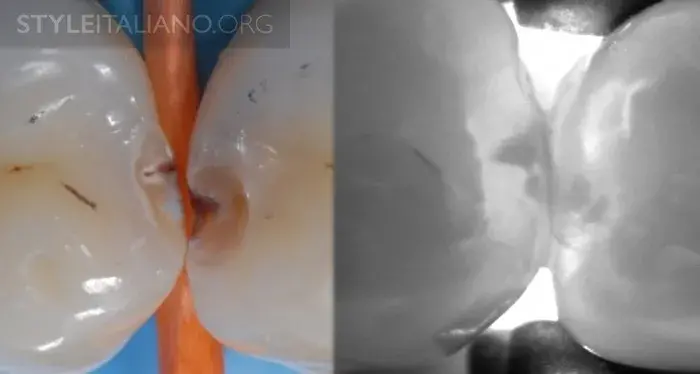

Рис. 15 — Предоперационный вид/ Лазерное просвечивание/ Рентген.

Рис. 16 – Просвечивание зубов показывает полости в истинном размере, а на рентгене они уменьшены.

Рис. 17 – Рентген слева, просвечивание справа.

Рис. 19 – Рентген и просвечивание.